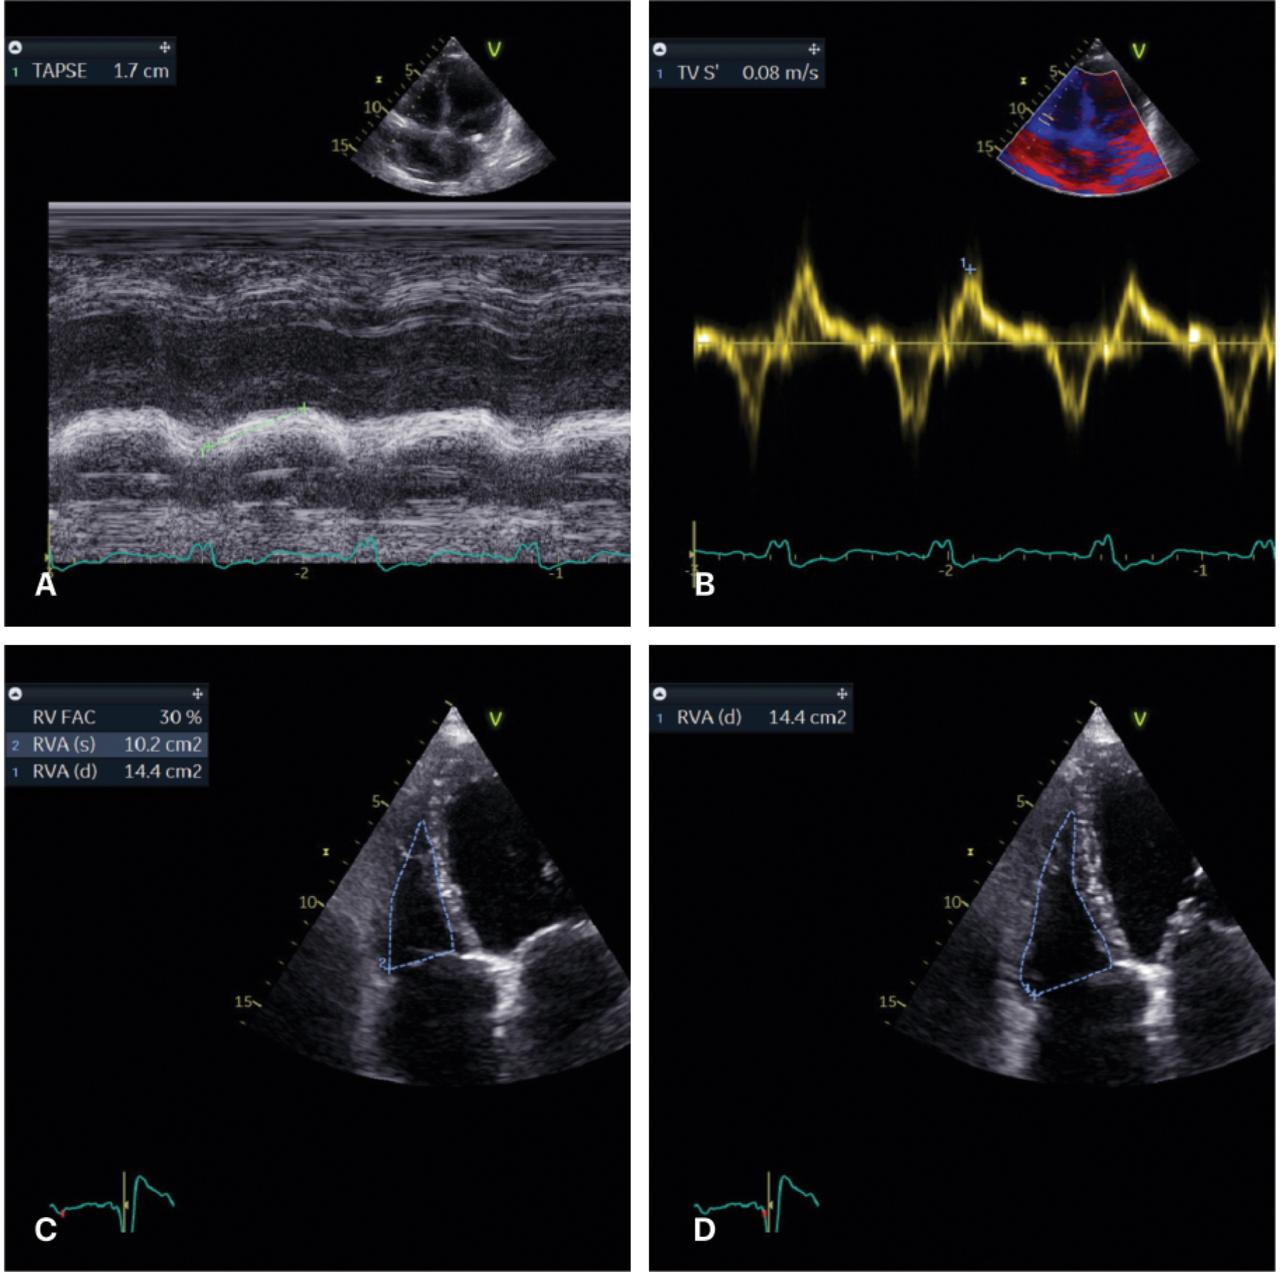

Figure 1